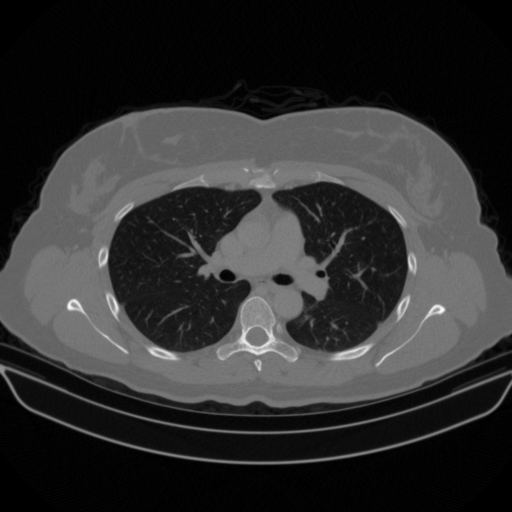

Reconstructed NATIVE CT scan (cycle consistency)

Full window (WL 1023.5, WW 4095 β†’ Low βˆ’1024, High +3071)

Actual HU range: [-1024.0, 1467.2]

Lung window (WL -600, WW 1500 β†’ Low βˆ’1350, High +150)

Actual HU range: [-1123.5, 150.0]

Mediastinum window (WL 40, WW 400 β†’ Low βˆ’160, High +240)

Actual HU range: [-160.0, 240.0]